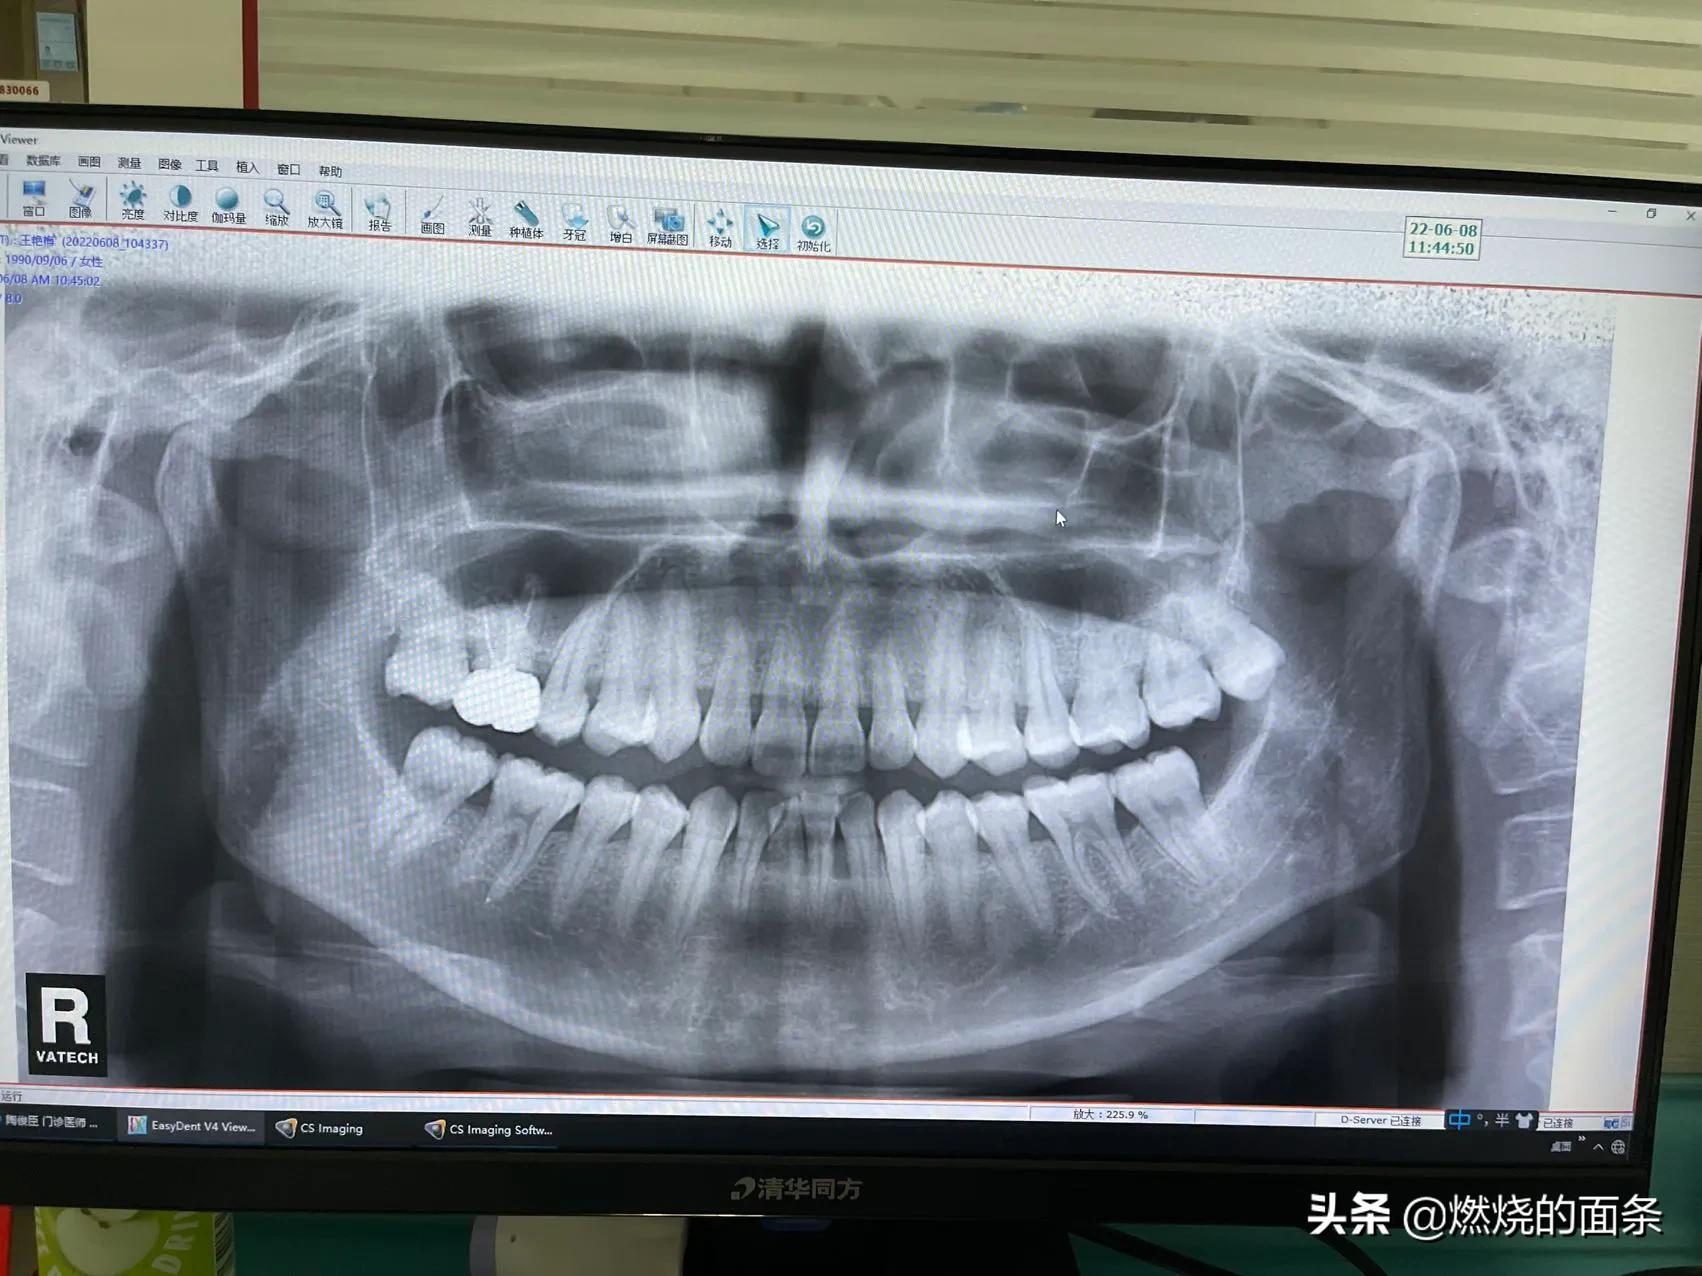

我的拍片,左边里面的智齿